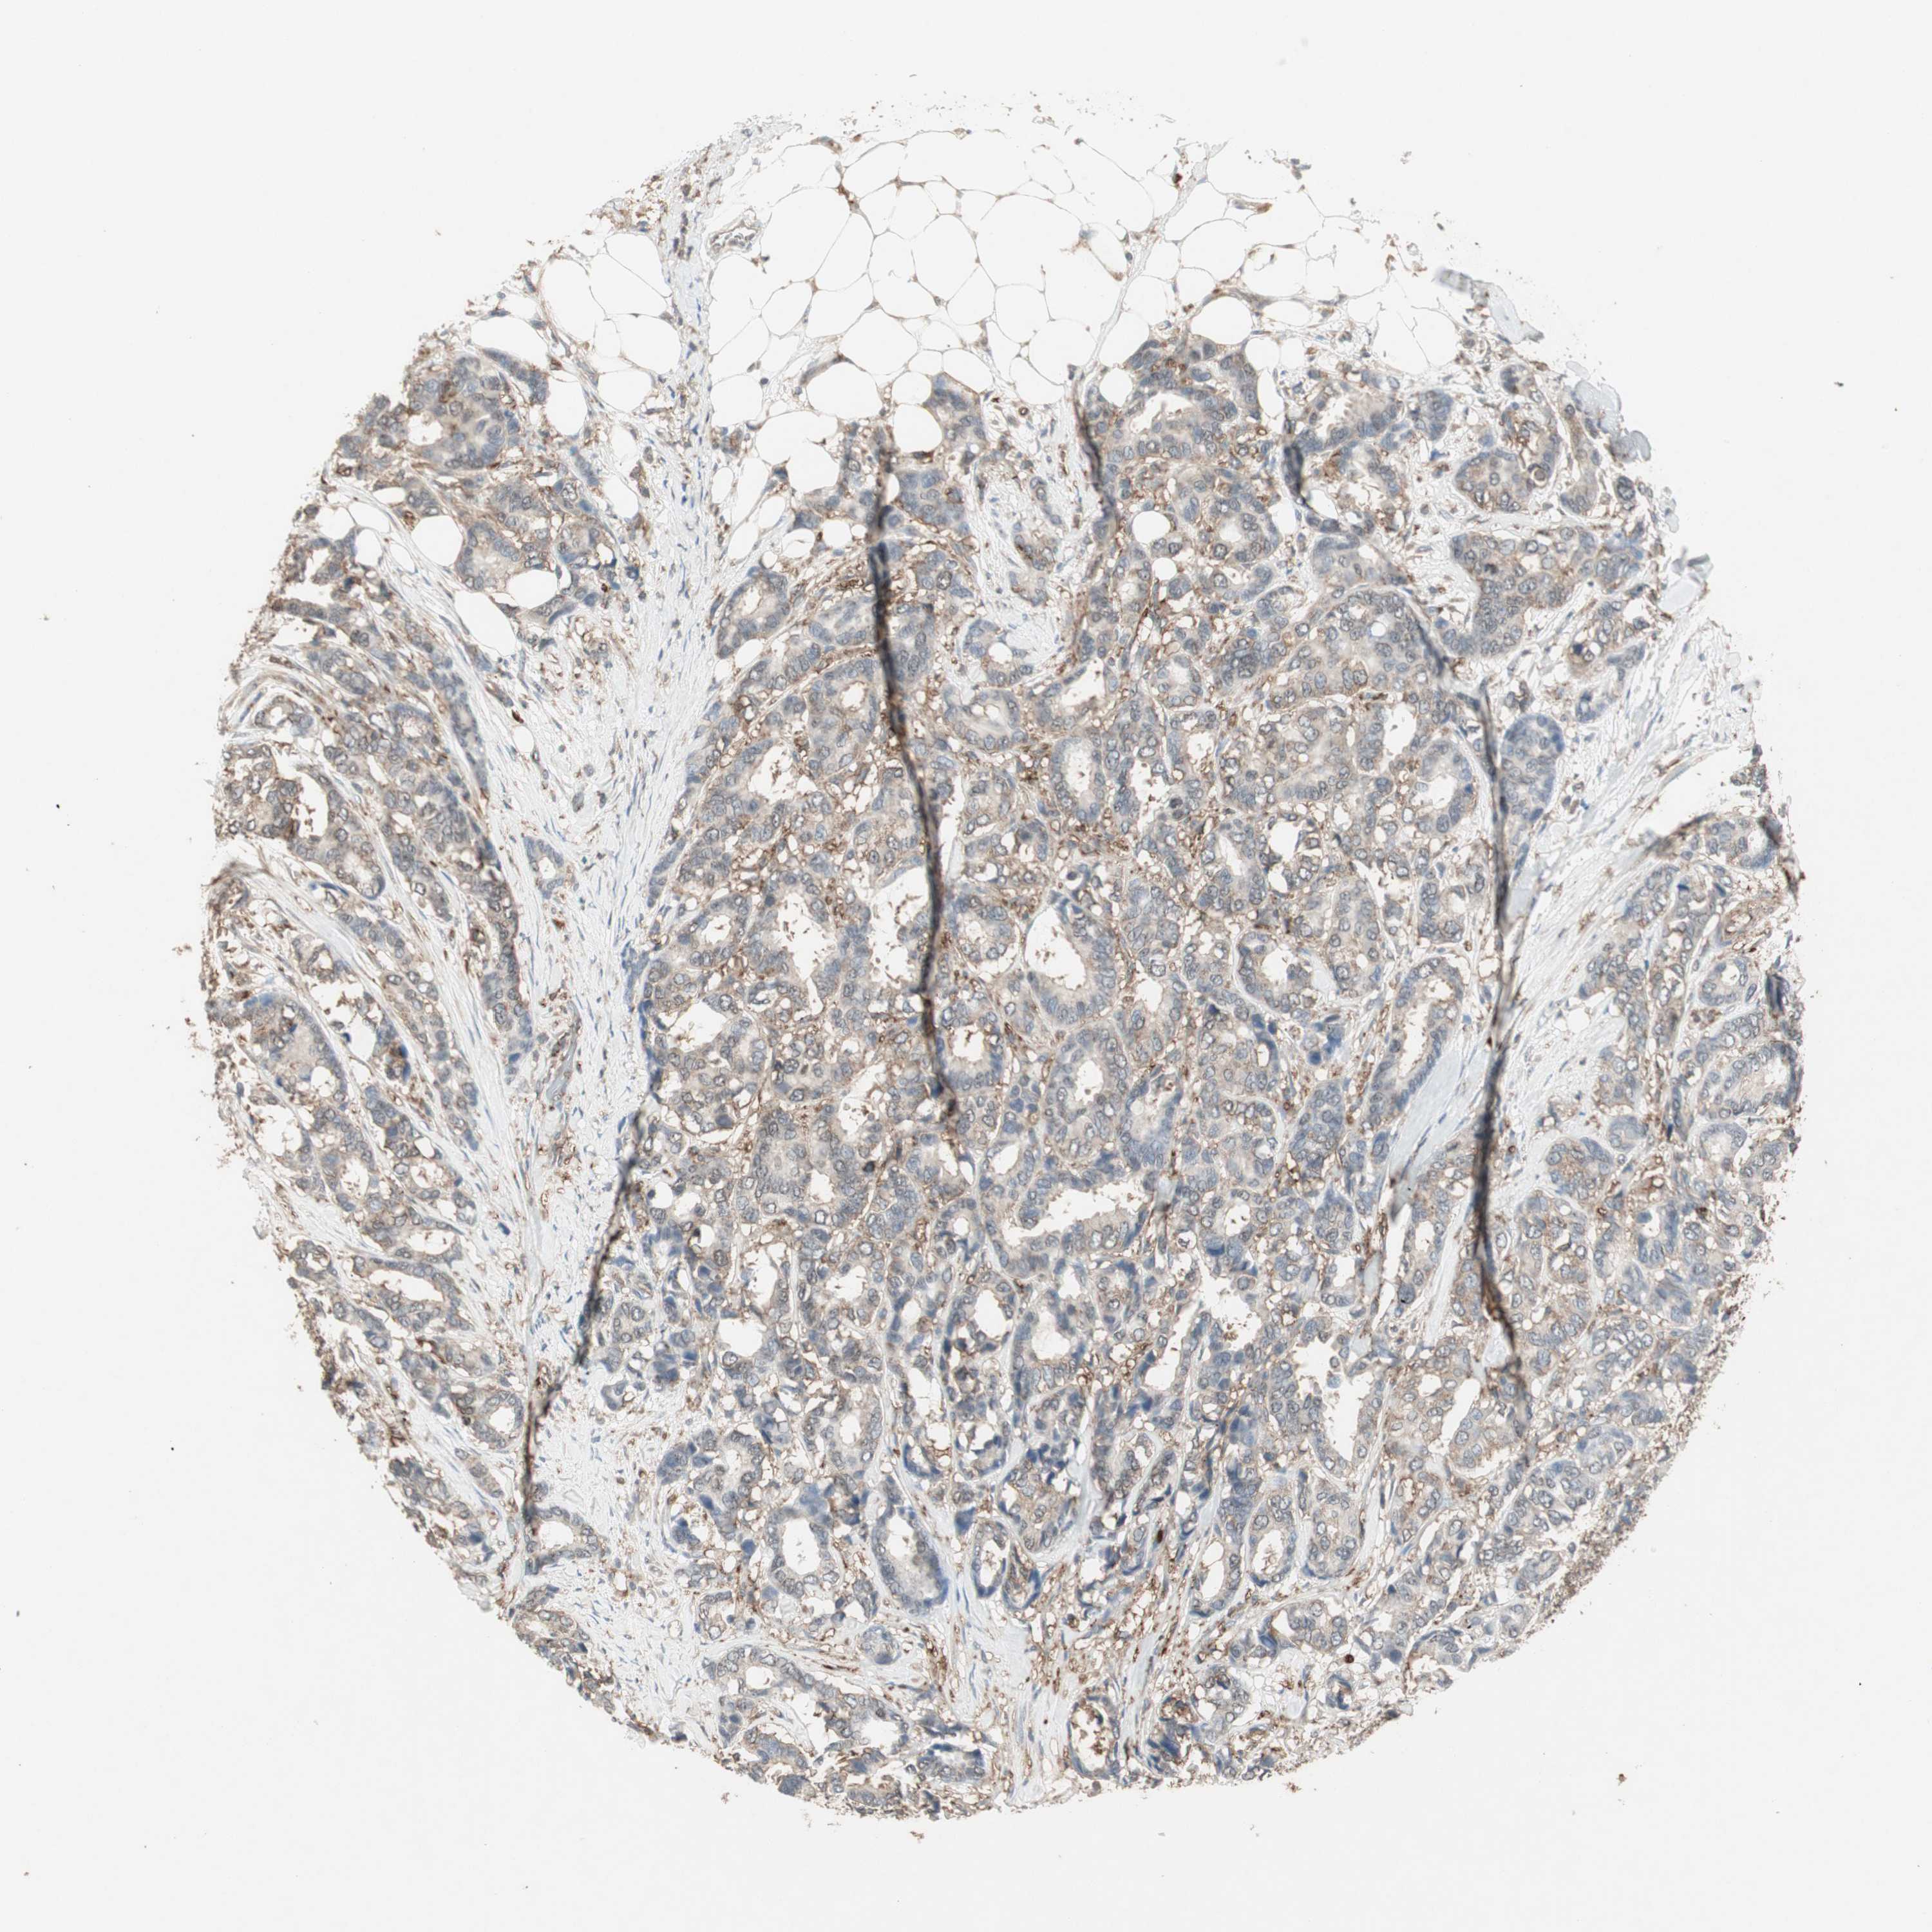

BRCA TCGA BRCA VALIDATION PROTEIN EXPRESSION